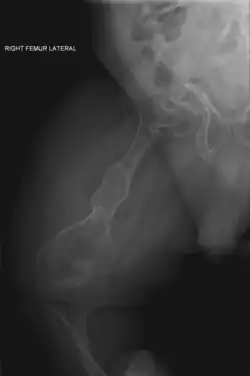

The main symptom of osteogenesis imperfecta is fragile, low mineral density bones; all types of OI have some bone involvement.[5] In moderate and especially severe OI, the long bones may be bowed, sometimes extremely so.[28] The weakness of the bones causes them to fracture easily—a study at the Endocrine Unit at the National Institute of Child Health in Karachi, Pakistan found an average of 5.8 fractures per year in untreated children.[29] Fractures typically occur much less after puberty, but begin to increase again in women after menopause and in men between the ages of 60 and 80.[1]: 486

OI type III causes osteopenic bones that fracture very easily, sometimes even in utero, often leading to hundreds of fractures during a lifetime;[24] early scoliosis that progresses until puberty; dwarfism (a final adult height frequently less than 4 feet or 120 centimetres); loose joints; and possible respiratory problems due to low rib cage volume causing low lung volumes.[5]: 1512

Diagnosis is typically based on medical imaging, including plain X-rays, and symptoms. In severe OI, signs on medical imaging include abnormalities in all extremities and the spine.[97] As X-rays are often insensitive to the comparatively smaller bone density loss associated with type I OI, DEXA scans may be needed.[5]: 1514

Rodding surgery is often done with the hope that it will offer a path to ambulation, walking, to patients with moderate or severe OI. A 2020 review in The Journal of Bone and Joint Surgery (JB&JS) found it remains broadly popular: ≈2⁄3 of people with OI types III and IV (severe OI) have undergone some form of rodding surgery in their lives, at a mean age of 4+1⁄10 and 7+1⁄2 years respectively;[25]: Table I one possible explanation for a tendency towards earlier intervention in type III is that one half of affected children could not walk at all without the surgery, as their limbs were more bowed, so surgery was sought sooner.[25]

In those with type III OI who had undergone rodding surgery, 79.5% had the femurs and tibias of both legs rodded.[25]: Table I The most common form of rods used are intramedullary (IM) rods, some of which, such as the Fassier–Duval IM rod, are telescoping, meaning that they are designed to grow as the child grows, in an attempt to avoid the necessity of revision surgeries.[118] Telescoping IM rods are widely used,[119] and the common Fassier–Duval IM rod is designed to be used to rod the femur, tibia, and humerus.[120]: 1 The surgery involves breaking the long bones in between one and three (or more)[119]: Figure 4 places, then fixing the rod alongside the bone to keep it straight.[120]: 11